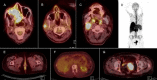

Figure 1

(A) FDG PET/CT of an 87-year-old male with noncutaneous melanoma (NCM) in the right nasal cavity with extension to adjacent sinuses (case 9). (B) FDG PET/CT of a 54-year-old male with NCM, presenting after resection of left parotid mass. (Additional metastatic lesion is noted in the right parotid, not recognized on patient’s CT scan, case 21). (C) A 40-year-old male with NCM of right tonsil. (FDG PET/CT reveals residual disease at the site of right tonsillectomy as well as metastatic lymph nodes in right cervical zone II, case15). (D) MIP image of a 74-year-old female with vulvar NCM revealing extensive metastases, case 20. (E) FDG PET/CT of a 66-year-old female with NCM in the anal canal (case 18). (F) FDG PET/CT image of a 32-year-old female with NCM of unknown primary currently revealing metabolically inactive sclerotic bone lesions in the site of previously lytic bone metastases, indicative of complete response to treatment (case 22). (G) FDG PET/CT image of the patient in MIP image (D), revealing local recurrence (case 20)